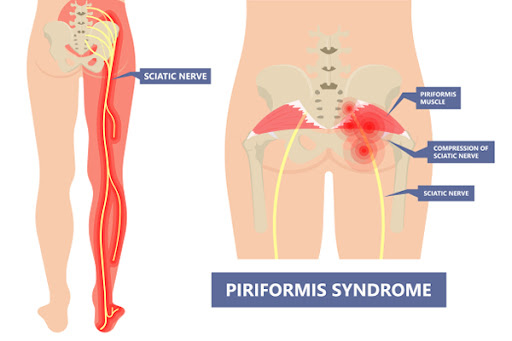

신경 압박

다리를 꼬고 앉을 경우 좌골신경에 압력이 가해져 좌골신경통이나 신경 손상이 발생할 가능성이 높아집니다. 이는 다리 저림, 통증 및 움직임 제한을 유발할 수 있습니다.

신경통

좌골신경이 압박을 받으면 다리 저림과 통증이 발생할 수 있으며, 심한 경우 일상생활에 큰 지장을 줄 수 있습니다.